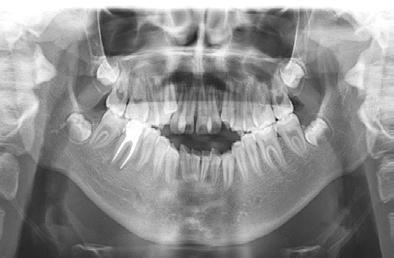

En la radiografía panorámica se observa 28 piezas dentales, con un diastema en los incisivos centrales (Figura 5).

En la radiografía panorámica (Figu ra 6) se observan 32 dientes, con los terceros molares en formación, adicionalmente la molar 46 con una

zona radiopaca compatible con tra tamiento endodóntico.